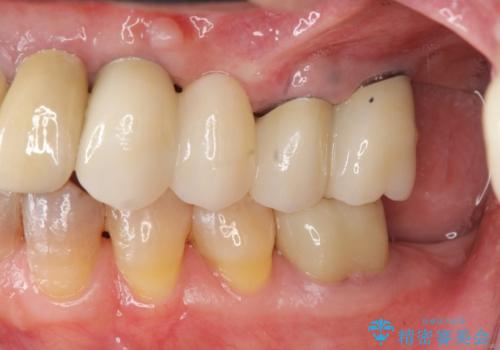

上顎は、残っている前歯も揺れがあり残すためにはクラウンでつなぐ歯周補綴が必要な状態です。

また咬合負担に不安のある前歯を助けるためにも、臼歯部にインプラント補綴を行いしっかりとかめる状態とすることも大切です。